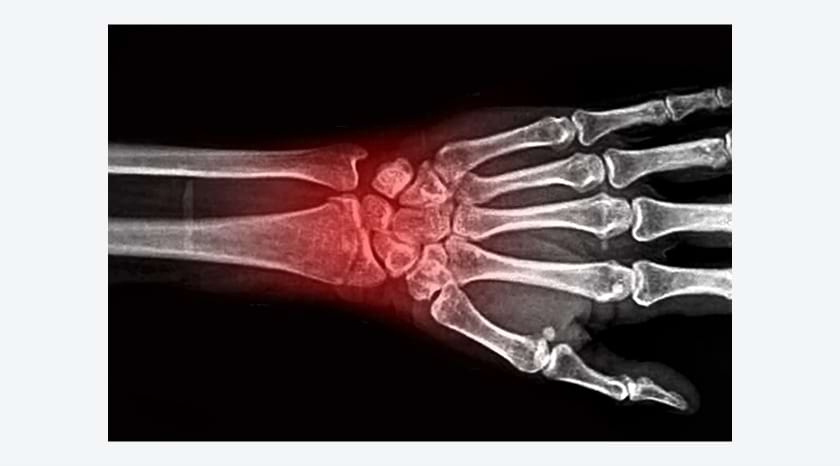

骨質疏鬆通常讓人聯想到脊椎或髖關節骨折,然而,手腕骨折(遠端橈骨骨折)同樣是一個重要的警示。易受影響的高危族群包括中老年人(尤其是更年期後或過早停經的女性)、有骨折家族史、長期使用類固醇或抗癲癇藥物、體重過輕、缺乏鈣質和維生素D、運動不足或長期臥床人士。了解手腕骨折與骨質疏鬆的關聯,有助預防及治療這種骨骼疾病。

手腕骨折通常發生在跌倒時本能地用手支撐地面,導致橈骨末端承受過大力量而骨折。除了因運動撞傷、滑倒或交通事故引起,也跟年齡及骨質疏鬆相關1,2。隨著年紀老化,鈣、磷等礦物質含量減少,骨小樑變得疏鬆,抗骨折能力會下降。很多時候,患者到發生骨折後,才發現自己已患上骨質疏鬆。

骨質疏鬆沒有症狀,不會引起疼痛,因此不易被察覺。然而,在低創傷的情況下,比如在平地跌倒就已骨折,很可能就是骨質疏鬆的警號。早前一位六十多歲的女病人在浴室滑倒後手部腫脹變形,被診斷為遠端橈骨骨折及骨質疏鬆,需接受手術及藥物治療。手術後,雖已不需特別固定患處,但仍需進行疼痛管理和炎症控制,並避免過早或不當的活動,以免影響骨骼癒合。